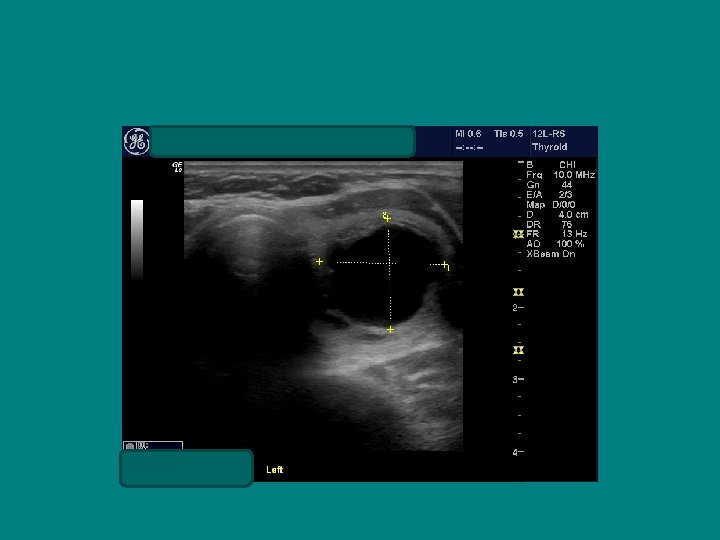

SEARCH FOR RECURRENT/RESIDUAL DISEASE • HYPOECHOIC MASS, LIKELY LYMPH NODE • AP/T 0. 7 CM !!

POST THYROIDECTOMY NECK Ø MEDIAL MOVEMENT OF CAROTID AND JUGULAR Ø Thyroid bed is filled with HYPER echoic connective tissue Ø This demarcates it from recurrence or metastatic lymph nodes which will be HYPO echoic

AP/T 0. 79/1. 45= 0. 54 !